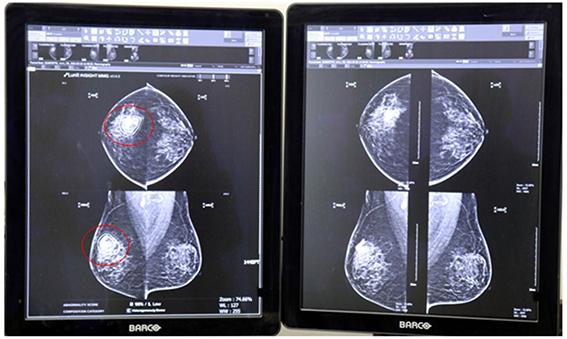

한국건강관리협회(이하 건협)는 유방촬영에서의 판독오류를 줄이고 정확도를 높이기 위해 지난 3월 19일 인공지능(AI)판독보조시스템 루닛 인사이트 MMG를 전국 16개 지부 건강증진의원에 도입했다.

이 판독보조시스템은 유방암 의심 부위를 검출하여 위치 정보와 의심 정도를 표기해 영상의학전문의의 진단을 보조하는 시스템이다. 특히 유방 조직의 밀도에 따라 나타날 수 있는 판독오류를 AI로 최소화해 정확한 판독과 진단에 활용하게 된다.

건협 광주전남지부 문운현 영상의학전문의는 “여성암발생 1위인 유방암은 조기에 발견하고 치료하는 것이 무엇보다 중요하다. 유선조직이 촘촘하게 모여 있는 치밀유방의 경우 유방암 병소가 조직에 가려져 판독에 어려움이 있을 수 있는데 이번 인공지능(AI)판독보조시스템 도입으로 유방암을 조기발견하는 데 도움이 될 것이라 기대한다”고 말했다.